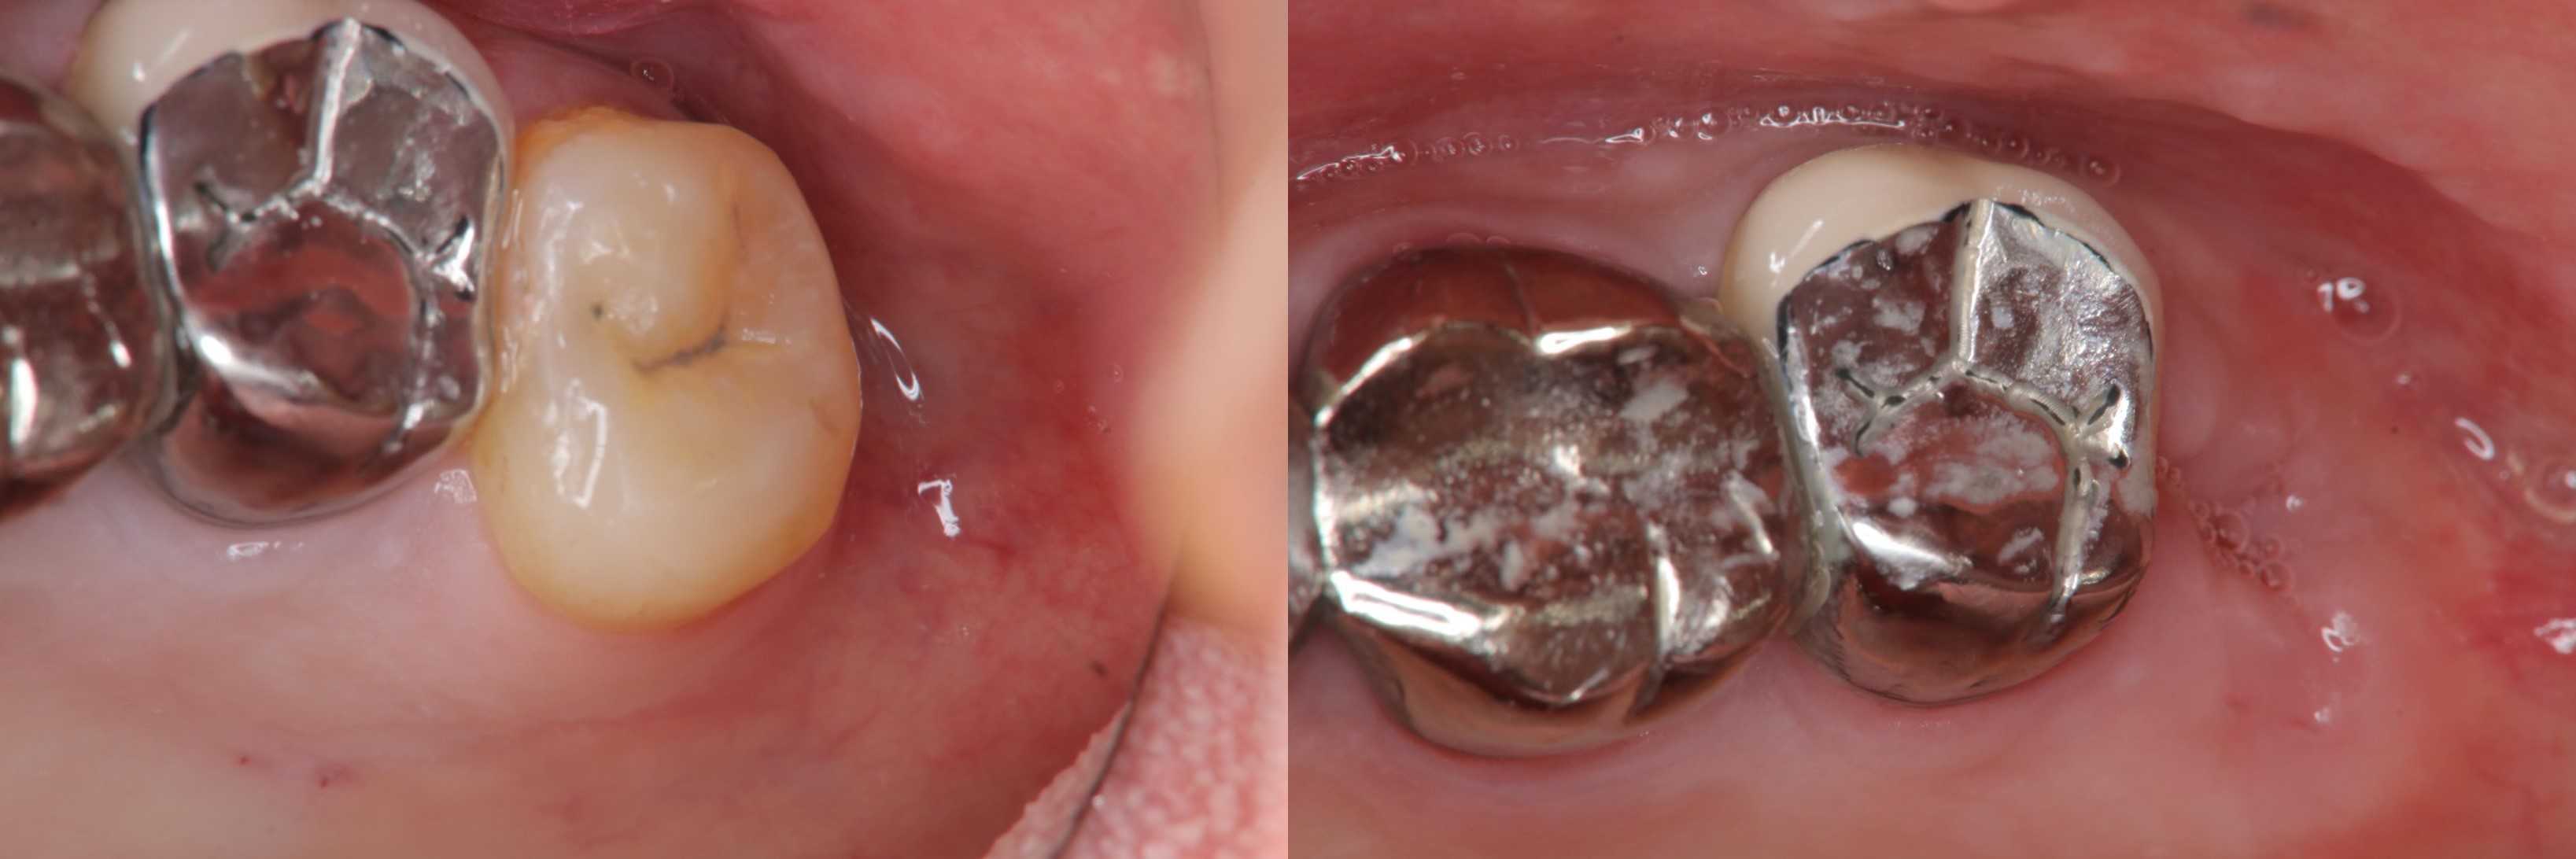

術前、術後比較

治療前,左上阻生齒深度蛀牙

微創拔除阻生齒,骨膠原修復並縫合

1週後傷口癒合良好